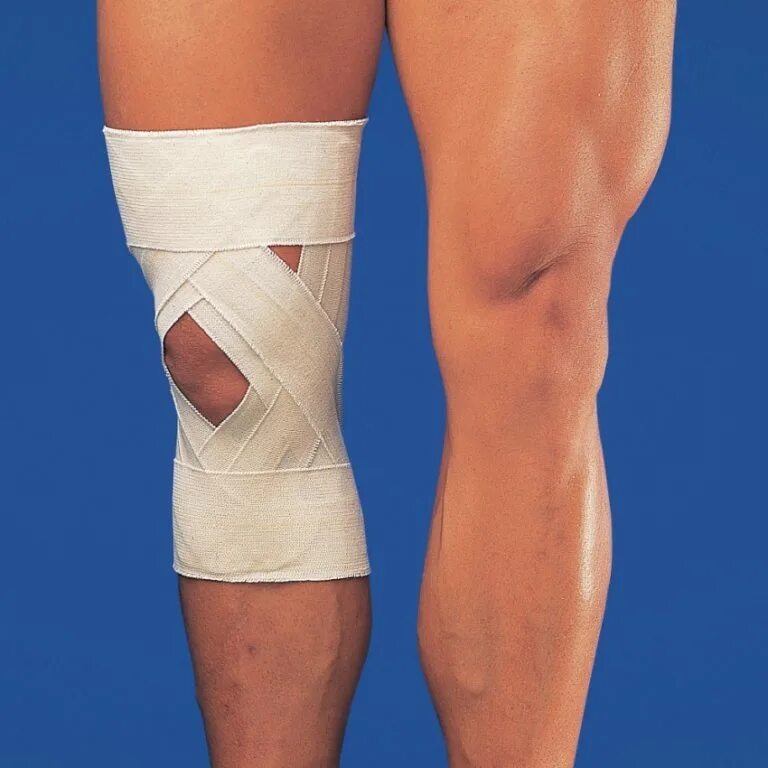

Дисторсия коленного